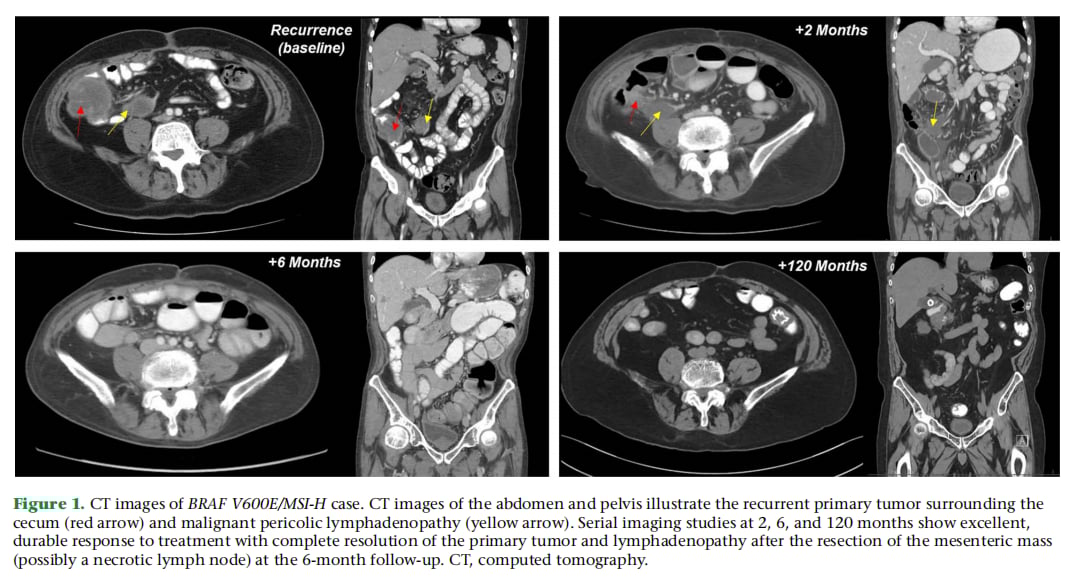

- 快速起效: 治疗开始仅约2个月,CT扫描显示复发病灶几乎完全消失。

- 长期缓解: 尽管治疗过程中因副作用经历了药物减量、停药和手术干预,但在长达120个月(整整十年)的随访中,患者始终保持着影像学上的完全缓解状态,未见疾病复发证据。

▲图1 BRAF V600E/MSI-H病例的CT影像